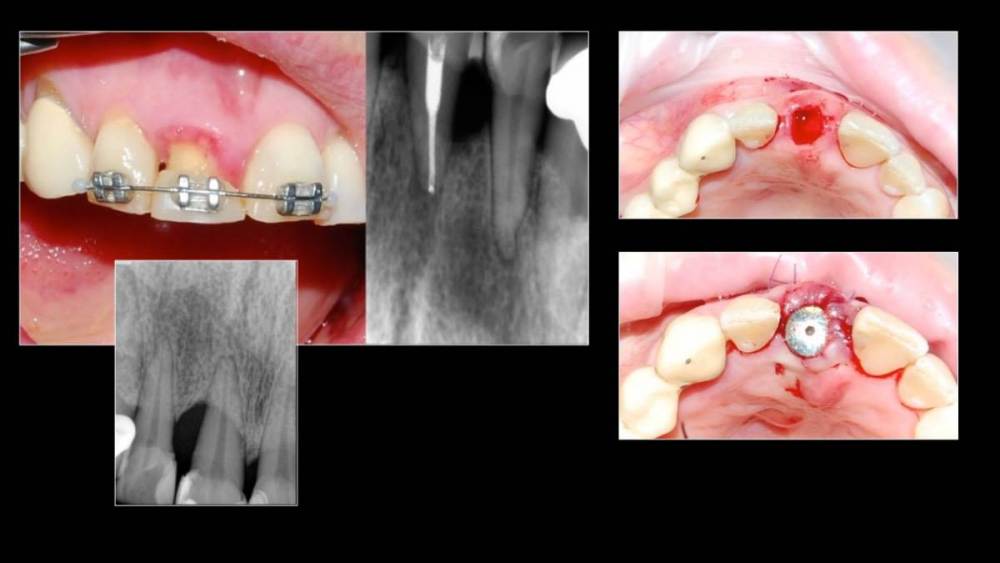

Владмир Опубликовано 20 марта, 2023 Автор Поделиться Опубликовано 20 марта, 2023 Здравствуйте коллеги. Работе 10 лет. Фото начальных этапов добавил 7 1 2 Ссылка на комментарий